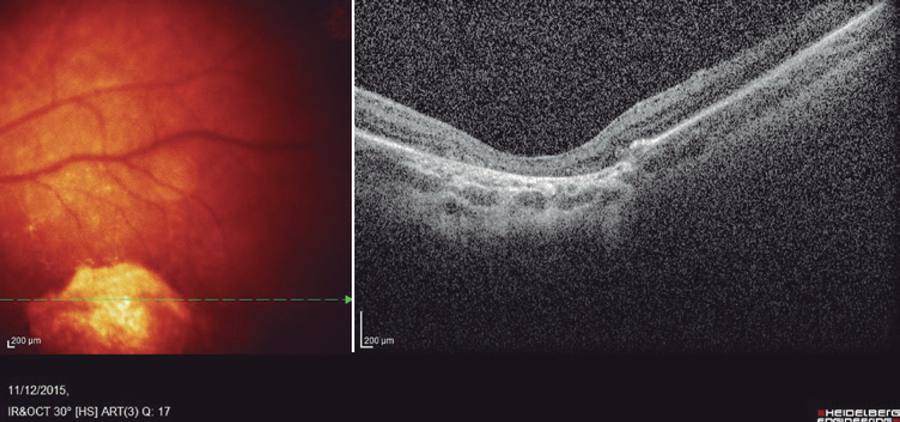

The ophthalmological exam was normal except for the presence of a single area of well-defined chorioretinal atrophy in the macula of the left eye. OCT (Spectralis OCT, Heidelberg Engineering, Germany) of the lesion demonstrated atrophy of the outer retina, including the outer nuclear layer and ellipsoid zone, associated with retinal pigment epithelium (RPE) hyper-reflectivity and increased penetration of OCT into deeper layers of the choroid and sclera (Figure 1).

Figure 1 Spectral domain OCT of a macular lesion in an infant with presumed Zika virus-associated microcephaly, demonstrating retinal thinning with atrophy of the outer retina, including the outer nuclear layer and ellipsoid zone, associated with retinal pigment epithelium hyper-reflectivity and increased penetration of OCT into deeper layers of the choroid and sclera.